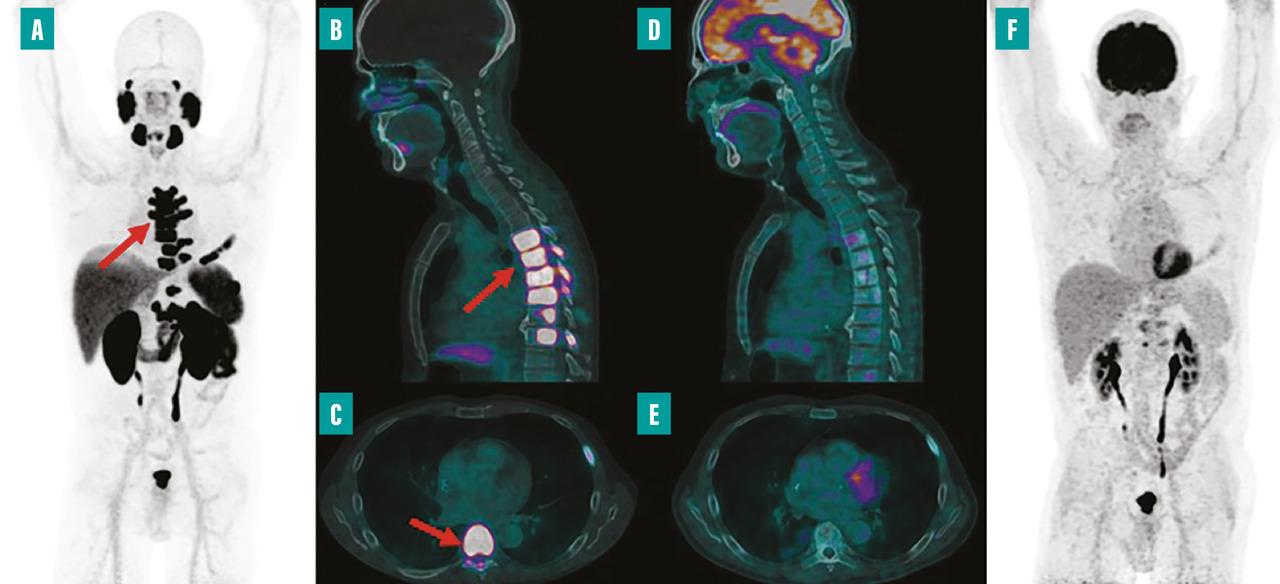

La médecine nucléaire, depuis ses débuts, a joué un rôle non seulement en imagerie mais aussi en thérapie, notamment grâce à la radiothérapie interne vectorisée (RIV). L’iode 131, utilisé depuis longtemps pour traiter les troubles thyroïdiens, illustre bien cette dimension thérapeutique fondamentale de la discipline. Ce traitement a introduit le concept de théranostique, qui consiste à visualiser précisément la maladie avant de la traiter et ainsi à sélectionner les patients avec le phénotype le plus adapté (ceux avec la plus forte fixation) pour maximiser l’efficacité thérapeutique. Actuellement, la RIV est également appliquée dans le traitement des tumeurs neuro-endocrines et, depuis peu, dans le cancer de la prostate. En effet, en 2023, Pluvicto (lutécium [177Lu] vipivotide tétraxétan) a été approuvé pour le traitement du cancer de la prostate métastatique, résistant à la castration après échec du traitement par hormonothérapie et chimiothérapie (fig. 2).15 Les recherches actuelles examinent l’intégration de la RIV avec des thérapies ciblées et étudient son utilisation en première ligne de traitement.